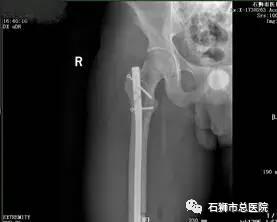

股骨骨折

股骨粗隆间粉碎性骨折

在学科建设提升技术方面,骨科这两年没有停止步伐。近年来,骨科对常见四肢骨折均能熟练进行接骨板或髓内针内固定术;对关节内骨折的诊断和治疗具有丰富的临床经验,尤其在促使老年骨折患者减少卧床时间、促进骨折愈合减少并发症发生取得良好临床效果。这些成绩,在陆陆续续健康出院的患者、及他们送来的感谢信中得到验证。